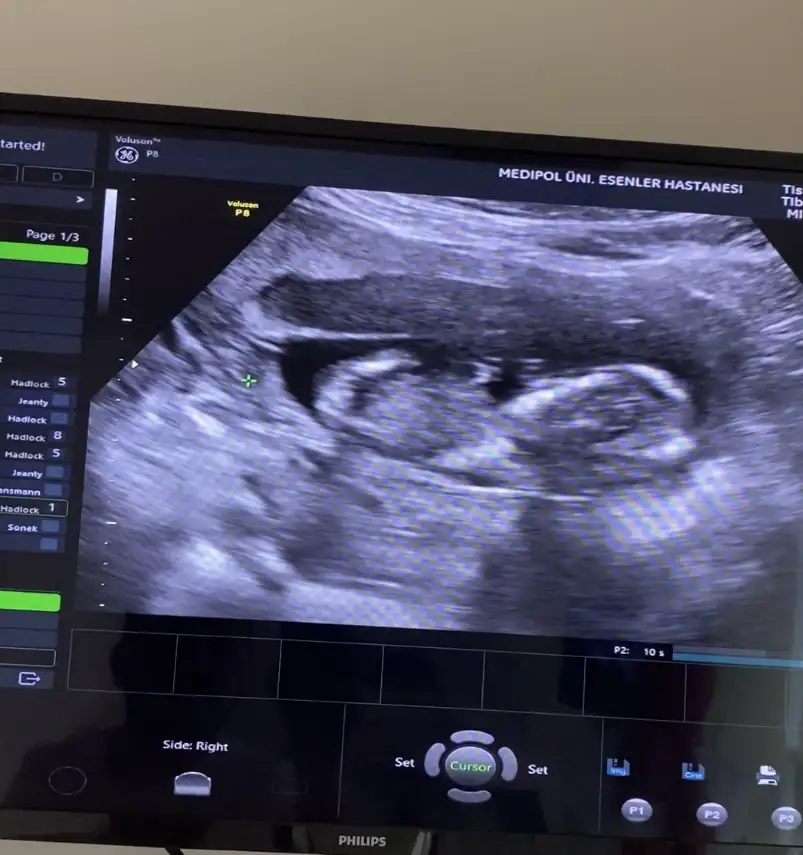

Bacak arası gibi ama çekimden mi bu kadar büyük bacakları, belki de değildir. Normalde böyle kalın ve kısa oluyorlarsoyasosu vu 14. Haftalıkken kendi doktorum 2. Bebegin poposunu görememişti ekrana sığmıyo diyerek bende videodan inceledim üstteki bebege bakarken alttaki bebegin bacak arası değilmi o benmi yanlış görüyorum

Vidodan baktım kesiin bacak arası canım ilk fotodakide bacak arası farklı bi açı orda çıkıntı var klitoris olsa 14. Haftada kaybolurdu heralde bilemedim iyiceBacak arası gibi ama çekimden mi bu kadar büyük bacakları, belki de değildir. Normalde böyle kalın ve kısa oluyorlarbaşka varsa atarsan bakarız birlikte

Burada hiç anlayamadımVidodan baktım kesiin bacak arası canım ilk fotodakide bacak arası farklı bi açı orda çıkıntı var klitoris olsa 14. Haftada kaybolurdu heralde bilemedim iyice

Devlet bişey vermedi görmedimde bugün kızda bacak arası daha boş ordan belli gibi kendi doktorum o gün kemik yapısına göre kıza benzettiğini söylemişti diğerini göremedim dedi ama videoda bi çıkıntı gördüm ben şimdi detaylı baktım cumartesi giderim netleşir inşallahBurada hiç anlayamadımama erkek olunca anlamak çok kolay oluyor. Videoda 3 çizgi belli mi kızda